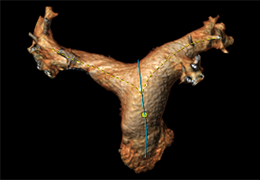

ANYTHINK 经导管主动脉瓣膜置换术分析系统